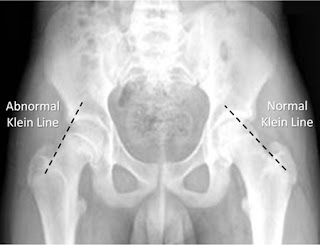

AP Radiograph of Pelvis in an skeletally maturing patient

There is a mild slip of upper femoral epiphysis with a positive Trethrowan's sign shown up by drawing a Klein's line up the lateral border of femoral neck and noting it doesn't intersect epiphysis.